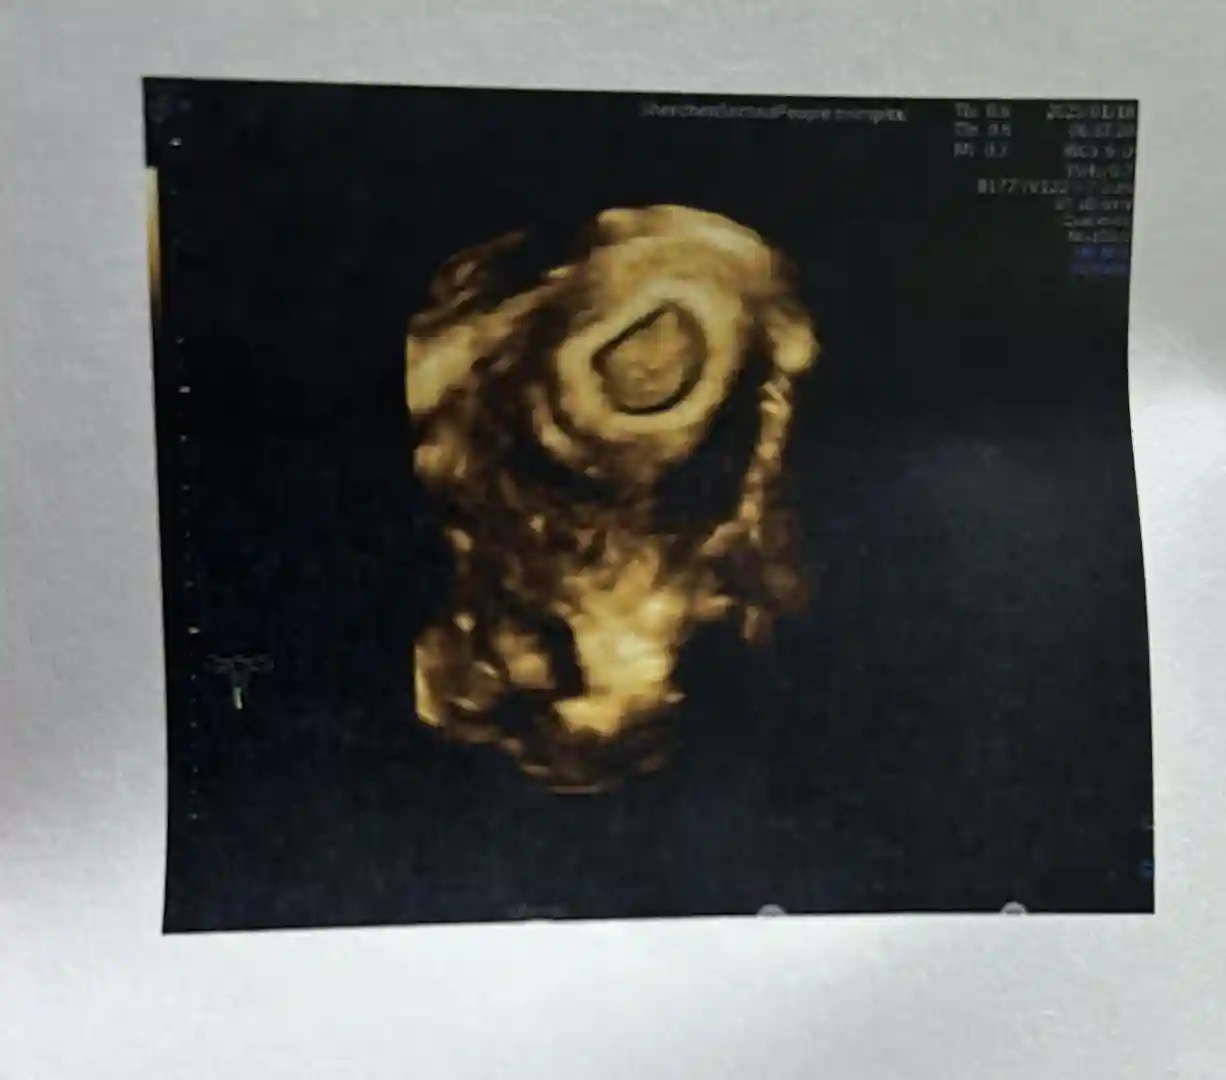

胎芽达到9mm了,看胎芽发育表,这个数据非常标准,开心❤️而且一直徘徊在2.6几的促甲状腺刺激素也恢复正常了!

但是我6w➕3开始有少量褐色分泌物,断断续续的,医生让我继续吃孕酮,从发现怀孕当天已经吃到现在了,孕酮数值一直很好,可能医生是因为觉得我年龄大(34岁一胎)检查让我继续吃。

年前再b超一次,8周多再见面咯我的宝宝